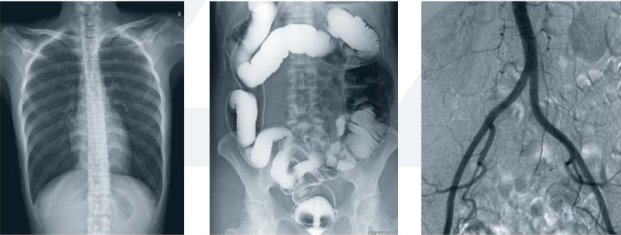

數(shù)字平板胃腸機屬于多功能X線機,除具有傳統(tǒng)胃腸機所有功能外,還有DR平板探測器X線攝影所有功能,主要用于消化道對比造影、消化道吞咽造影、全脊柱拼接攝影、全下肢拼接攝影、ERCP、泌尿系造影、“T”管造影、鋇劑灌腸、四肢造影、子宮輸卵管造影等各類檢查,是檢查消化道潰瘍、腫瘤、異物等疾病的主要方法之一。

數(shù)字平板胃腸機不僅可以做普通的胃、食管鋇餐透視,胸腹部的常規(guī)透視檢查,而且圖像更清晰,多了數(shù)字化處理過程,還可以實時點片,更便捷的獲得實時圖像,及時抓拍住病灶圖像,為患者留存影像資料。這就像我們的手機抓拍瞬間圖像保存到手機相冊一樣,能夠診斷早期食道癌、胃癌、小潰瘍等疾病。